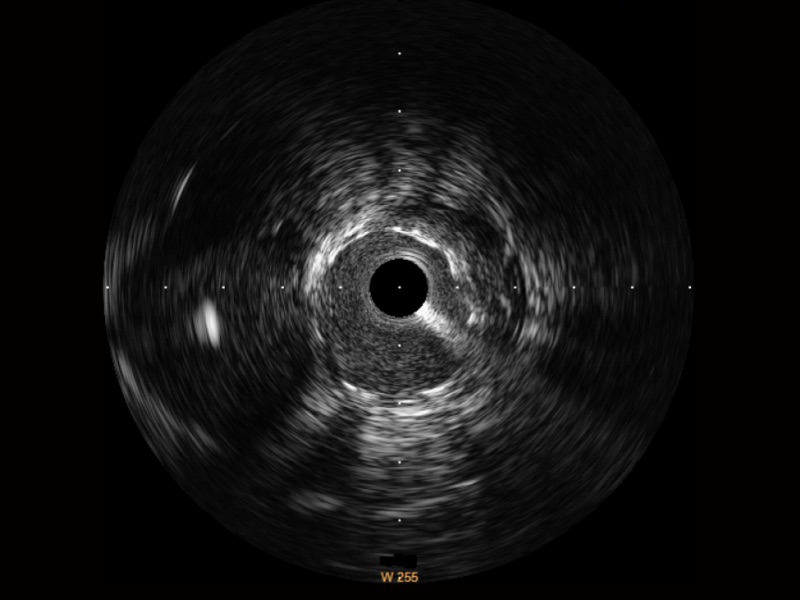

传统IVUS图像

对比传统IVUS导管成像,银河集团官网宽频IVUS图像的近场支架梁显影更细腻,远场中膜外血管仍清晰可辨,兼顾远中近,兼顾分辨力与穿透深度